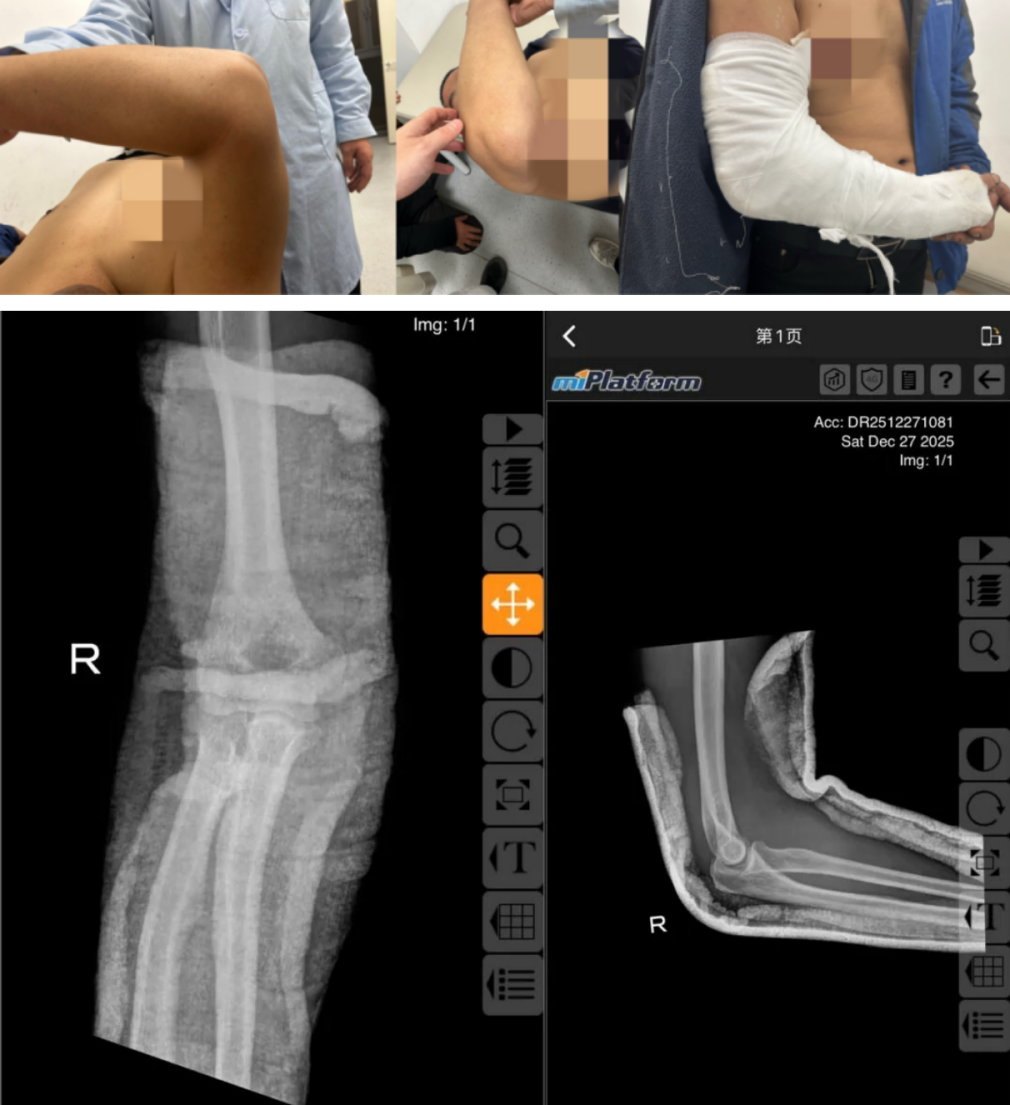

据了解,王先生因不慎摔倒导致右肘部严重受伤,当即感到剧痛,关节迅速肿胀畸形,活动受限。事发一小时内,在家属搀扶下赶往西安红会医院就诊,此时,伤处已高度肿胀,主动与被动活动完全受限,情况危急。接诊医师薛安邦迅速完成初步查体,结合DR影像,判断为右肘关节后脱位,随即联系手法复位室董博主任与周健副主任医师。团队凭借丰富经验快速确诊,并决定立即施行手法复位。“肘关节后脱位若延误治疗,可能加重肌肉痉挛、压迫血管神经,甚至引发前臂缺血性肌挛缩等不可逆损伤。”董博主任细致向家属讲解病情与治疗方案,同时温和安抚王先生,“你放心,我们会尽量减轻你的痛苦,争取一次复位成功。”三位医护人员沉稳专业的态度,让患者与家属悬着的心渐渐落地。

由于王先生肘部肿胀严重、疼痛剧烈,给复位操作增加了不小难度。薛安邦医生先为患者摆放好舒适体位,为复位顺利开展筑牢基础。复位过程中,董博主任稳健施力牵引,周健主任精准固定配合,薛安邦医生则从旁安抚引导。随着一声标志复位的“咔嗒”轻响,肘关节成功归位,王先生的疼痛即刻大幅缓解,手臂恢复部分活动能力。复查DR影像显示,肘关节已完全复位,关节间隙恢复正常。随后,薛医生为患者完成石膏固定,并详细交代复位后注意事项。